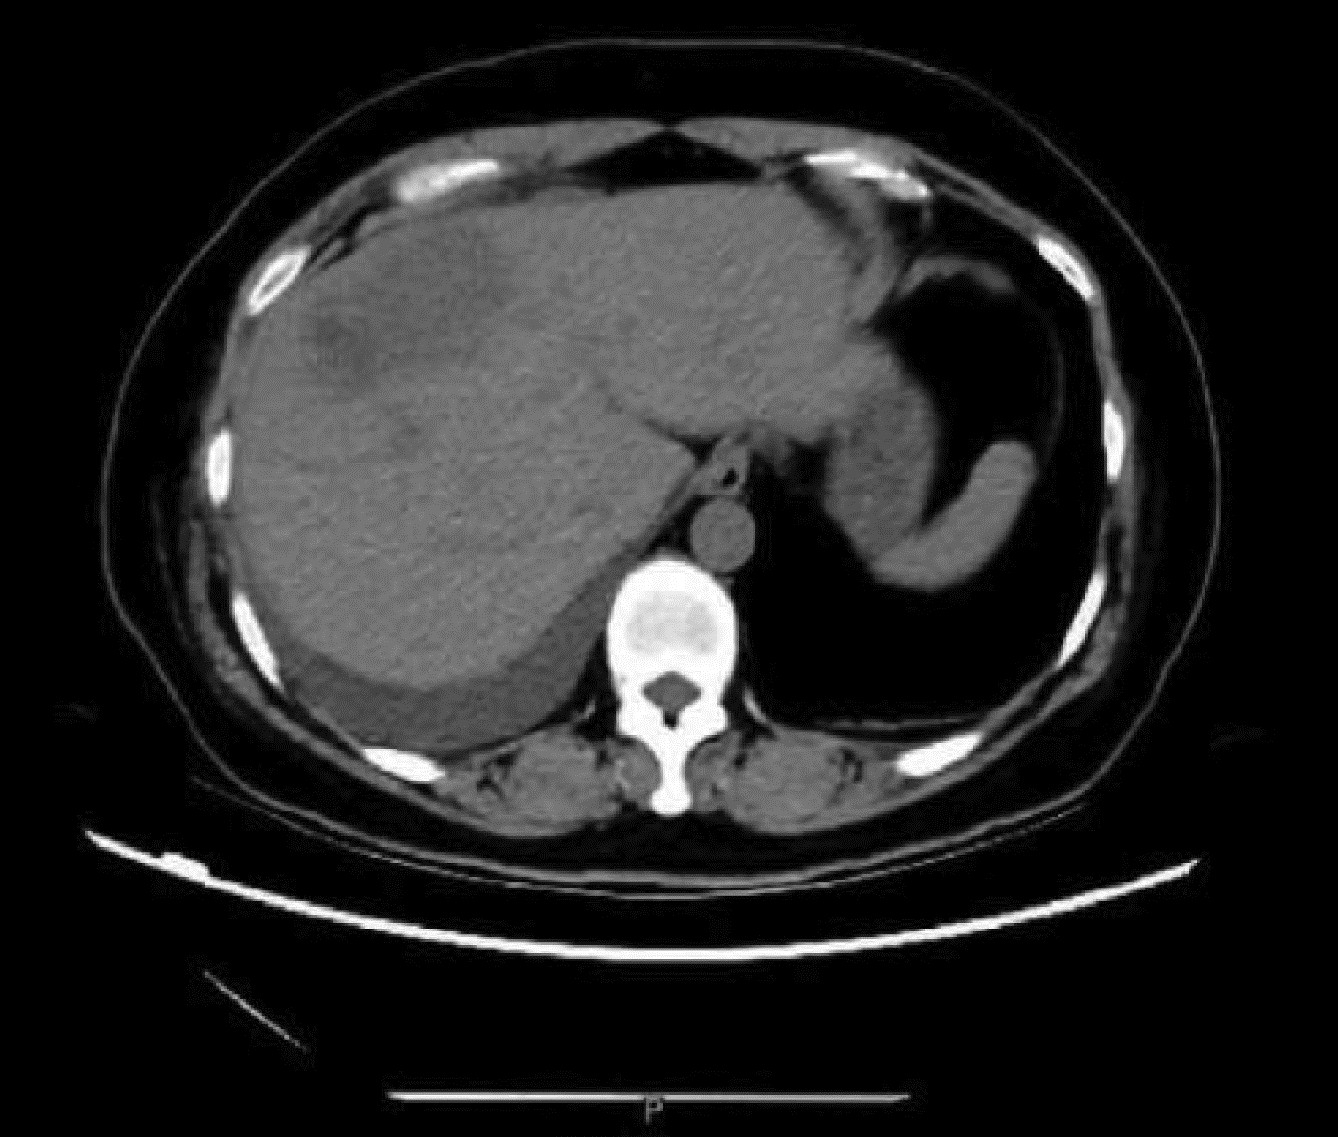

Massive hepatic hemangioma with diffuse arterioportal fistula: A case report

Bangjian ZHOU, Jun YANG, Yu YIN, Xiaoli ZHU, Caifang NI, Wansheng WANG

2023, 39(3): 640-643. DOI: 10.3969/j.issn.1001-5256.2023.03.025

Abstract(1037) HTML (228) PDF (3500KB)(109)

Abstract: